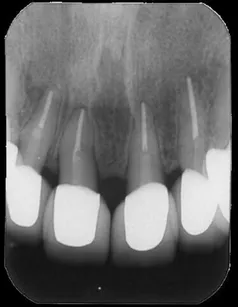

[症例1]

重度の歯周病で奥歯がすでになくなっており、そのため前歯もグラグラの状態でした。

右上の前歯(向かって左上)は自然に抜け落ちたそうです。

下の前歯の裏側には多量の歯石がたまっています。

【処置内容】

歯周初期治療、全体に歯周外科処置を実施、その後セラミックブリッジ、セラミッククラウン、

右上6・5番、左上3・4・5・6番、左下6番、右下4・6番にインプラントを実施。

• 治療期間:約2年

• 治療費:400万円

• 治療回数:30回